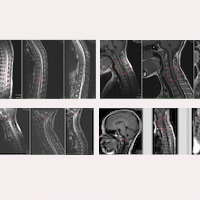

アーノルド・キアリI型症候群

脊髄空洞症

特発性脊髄空洞症